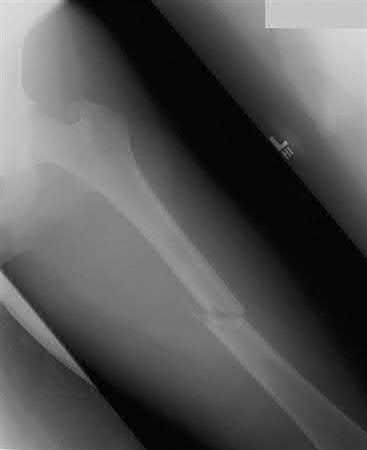

Which of the following will most likely result with the use of a fracture table when treating the injury shown in Figures A and B?

The fracture table has been shown to induce an internal malrotation deformity when it is used for treating femoral shaft fractures.

Intramedullary nailing with reaming of the bone and static locking of the nail is the treatment of choice for femoral shaft fractures in adults. The fracture table has been used with excellent results. Compared to manual traction, the fracture table provides an advantage as only one assistant is necessary.

However, it may limit access to the patient if other body areas are injured. Additionally, the fracture table has been shown to induce an internal malrotation deformity, which results from internally rotating the limb to facilitate access to the starting point and to improve visualization of the hip in the lateral plane. Rotation may also be difficult to assess clinically once the limb is positioned and draped.

Figures A and B are AP radiographs demonstrating a femoral shaft fracture. Incorrect Answers: